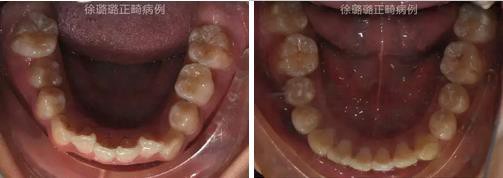

口內(nèi)特征:恒牙早期,雙側(cè)磨牙關(guān)系為輕度遠(yuǎn)中關(guān)系,前牙深覆牙合 Ⅱ°,深覆蓋 6mm,上下頜牙弓中線不端正,上頜中線右偏 3mm,上頜前牙唇傾,下頜牙列輕度擁擠,右側(cè)上頜間隙不足,左側(cè)乳尖牙滯留,上頜左側(cè)乳尖牙對(duì)刃牙合,上下頜牙弓形態(tài)不對(duì)稱。

X 線檢查:替牙列,上頜雙側(cè)尖牙埋伏阻生(含牙囊腫),四顆第三恒磨牙牙胚存在。

前牙 CT 檢查:上頜雙側(cè)尖牙埋伏阻生——雙側(cè)尖牙的牙冠均在側(cè)切牙根方的唇向位。